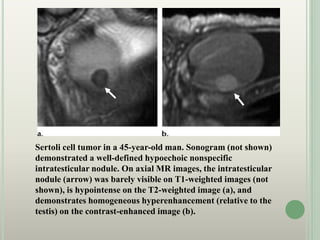

Sertoli cell tumor in a 45-year-old man. Sonogram (not shown)

demonstrated a well-defined hypoechoic nonspecific

intratesticular nodule. On axial MR images, the intratesticular

nodule (arrow) was barely visible on T1-weighted images (not

shown), is hypointense on the T2-weighted image (a), and

demonstrates homogeneous hyperenhancement (relative to the

testis) on the contrast-enhanced image (b).